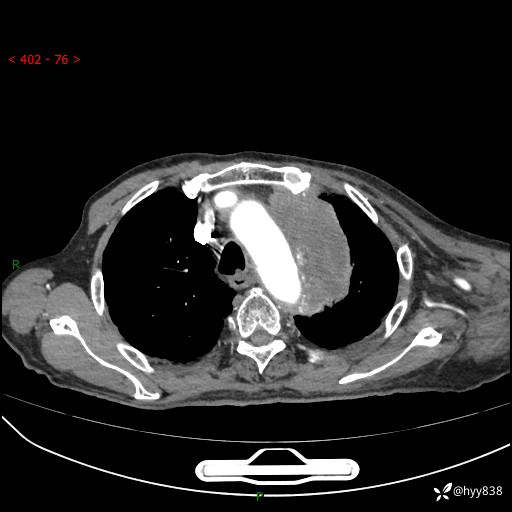

老年男性,气促5月,胸背痛2月。发现肺尖较大肿块,摧枯拉朽之势---结果公布~

现病史:患者于5月前饮酒后突发静息状态下气促不适,无胸闷、胸痛、发热、咳嗽、咳痰等不适,于当地第五人民医院及我院就诊,输液治疗后(具体不详)后气促稍缓解,遂出院后自行口服中草药治疗。近2月出现胸背痛,伴左上肢疼痛、乏力、感觉异常,稍有咳嗽、咳痰,咳黄痰、痰液粘稠,无咳血。为进一步诊治来我院。

胸部CT增强扫描(外院平扫)